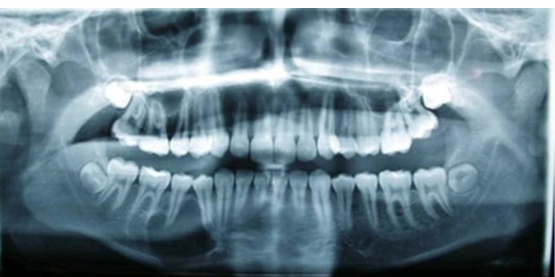

MFD EXAMS /23 6 1234567891011121314151617181920212223 You have 30 min to complete this exam. The timer will start once you begin Attention: Only a few minutes left! Please submit your answers soon. MFD 1 Get a quick sneak peek before the real exam !This trial quiz is designed to show you the question style, difficulty level, and how the options will appear on the platform. 1 / 23 1. What is the lethal dose and toxic dose of fluoride, management? Check 2 / 23 2. What the advantage of silver diamine over other methods and disadvantages ? Check 3 / 23 3. Method of topical fluoride application with concentration ? Check 4 / 23 4. What will happen if left untreated? Check 5 / 23 5. What changes that will happen if the habit stopped? Check 6 / 23 6. Give 3 of your initial stage of treatment? Check 7 / 23 7. What are the causes? Check 8 / 23 8. What is this? Check 9 / 23 9. Then they specified the type of pain and asked about the diagnosis Check 10 / 23 10. What other tests to check vitality of the pulp? Check 11 / 23 11. What are the factors will govern the Rx of Posterior cross bite ? Check 12 / 23 12. What are the factors that govern the treatment of anterior cross bite? Check 13 / 23 13. Name the appliance that you can use to treat this case? Check 14 / 23 14. Name 3 causes? Check 15 / 23 15. Name the most important clinical diagnostic information you need to know. (check RCSI intensive course )? Check 16 / 23 16. What do you see? Check 17 / 23 17. What is your treatment? Check 18 / 23 18. Name the investigations needed? Check 19 / 23 19. causes for gingival enlargement ? Check 20 / 23 20. What is the common side effect of this drug? Check 21 / 23 21. Name the drug that he may take to treat this condition? Check 22 / 23 22. The patient may have what? Check 23 / 23 23. What is this clinical condition? Check /31 2 12345678910111213141516171819202122232425262728293031 You have 30 min to complete this exam. The timer will start once you begin Attention: Only a few minutes left! Please submit your answers soon. MFD 2 Get a quick sneak peek before the real exam !This trial quiz is designed to show you the question style, difficulty level, and how the options will appear on the platform. 1 / 31 1. Mention 2 fixed space maintainers and 2 removable space maintainers other from mentioned : Check 2 / 31 2. Other space maintenance used for child lost primary second molar E before the eruption of the permanent molars ? Check 3 / 31 3. What are the difference between nance appliance and Transpalatal arch Check 4 / 31 4. What material used to attach band? Check 5 / 31 5. What instruction you give to patient? Check 6 / 31 6. Name other fixed space maintainer used in upper jaw and mechanism of their action? Check 7 / 31 7. What component of this appliance? Check 8 / 31 8. What is this appliance , for what its used ? Check 9 / 31 9. Treatment? Check 10 / 31 10. Define Abrasion and Erosion? Check 11 / 31 11. What does this picture show? Check 12 / 31 12. what investigations you can do ? Check 13 / 31 13. Drugs can lead to lichenoid reaction Check 14 / 31 14. What extra oral features in “ Lichenoid reaction )? Check 15 / 31 15. What microscopical features of it ( licheonoid reaction )? Check 16 / 31 16. Definitive diagnosis ? Check 17 / 31 17. Mention type of suggested biopsy ? Check 18 / 31 18. Mention 4 differential diagnosis ? Check 19 / 31 19. Mention 4 questions you will ask the patient ? Check 20 / 31 20. Give 4 intraoral decription of what you see ? Check 21 / 31 21. What the other surgery can be performed to make prothesis? Check 22 / 31 22. Can this tooth stand with fixed prothesis? (in the opg )à taken from Malek file ? Check 23 / 31 23. Radiograph of missing multiple teeth consider it according to Antes law? ON which tooth you will make Abutment ? Check 24 / 31 24. What is Antes law? Check 25 / 31 25. What is best one to use as abutment in fixed prosthesis A or B? Check 26 / 31 26. What relevance of this picture? Check 27 / 31 27. What’s complication of doing surgery in this area floor of mouth? Check 28 / 31 28. Other 2 radiograph needed in diagnosis? Check 29 / 31 29. Give 4 differential diagnosis? Check 30 / 31 30. What can you see ? Check 31 / 31 31. What is the name of radiograph? Check Your score is /30 1 123456789101112131415161718192021222324252627282930 You have 30 min to complete this exam. The timer will start once you begin Attention: Only a few minutes left! Please submit your answers soon. MFD 3 Get a quick sneak peek before the real exam !This trial quiz is designed to show you the question style, difficulty level, and how the options will appear on the platform. 1 / 30 1. Treatment? Check 2 / 30 2. Histopathology? Check 3 / 30 3. Differential diagnosis Check 4 / 30 4. Clinical features’? Check 5 / 30 5. Patient said, this lesion is very frequent, why? Check 6 / 30 6. What are the causes for ulcers? Check 7 / 30 7. Patient have other signs like uveitis ,Genital ulcerations which syndrome he had ? Check 8 / 30 8. Name of the lesion ? Check 9 / 30 9. Mention some TMJ movement ? Check 10 / 30 10. Blood supply ? Check 11 / 30 11. Nerve supply ? Check 12 / 30 12. Which muscles close? Check 13 / 30 13. Action of open and open wide? Check 14 / 30 14. Why it’s Atypical joint ? Check 15 / 30 15. Name of the ligaments ? Check 16 / 30 16. What would be your management? Check 17 / 30 17. Bacteria involved Check 18 / 30 18. Which type of Periodontitis? Check 19 / 30 19. Treatment? Check 20 / 30 20. Histopathology? Check 21 / 30 21. Differential diagnosis? Check 22 / 30 22. Clinical features? Check 23 / 30 23. What are the time frames for making a complaint? Check 24 / 30 24. What are the 3 points related to negligence? Check 25 / 30 25. Who is allowed access to the patient records? Check 26 / 30 26. How to differentiate if it is upper or lower motor neuron lesion? Check 27 / 30 27. Management? Check 28 / 30 28. What are the causes? Check 29 / 30 29. What should you advise the patient to do? Check 30 / 30 30. What is this lesion? Check Your score is /24 1 123456789101112131415161718192021222324 You have 30 min to complete this exam. The timer will start once you begin Attention: Only a few minutes left! Please submit your answers soon. MFD 4 Get a quick sneak peek before the real exam !This trial quiz is designed to show you the question style, difficulty level, and how the options will appear on the platform. 1 / 24 1. What does MRONJ stands for? Check 2 / 24 2. Give definition for MRONJ Check 3 / 24 3. For what medical problems these medications are used? Check 4 / 24 4. Stages of MRONJ 3 Check 5 / 24 5. What’s this appliance? Check 6 / 24 6. At what age is it used? Check 7 / 24 7. What type of malocclusion is it used to treat? Check 8 / 24 8. What changes will produce? (4 options) Check 9 / 24 9. Disadvantages? Check 10 / 24 10. Why is it flabby tissue? Check 11 / 24 11. what is this condition called? Check 12 / 24 12. Causes ? Check 13 / 24 13. Clinical Features ? Check 14 / 24 14. How to avoid it ? Check 15 / 24 15. Management? Check 16 / 24 16. Ideal post length and width Check 17 / 24 17. Definition of Ferrule it’s the Check 18 / 24 18. What is the importance of the ferrule effect ? Check 19 / 24 19. Describe the radiolucency? Check 20 / 24 20. Give 6 differential diagnosis? Check 21 / 24 21. Give 5 radiographical features? Check 22 / 24 22. What is the difference between incisional and excisional biopsy? Check 23 / 24 23. What other 2 plain radiographs we can we can take? Check 24 / 24 24. ALARA? Check Your score is /22 1 12345678910111213141516171819202122 You have 30 min to complete this exam. The timer will start once you begin Attention: Only a few minutes left! Please submit your answers soon. MFD 5 Get a quick sneak peek before the real exam !This trial quiz is designed to show you the question style, difficulty level, and how the options will appear on the platform. 1 / 22 1. . Types of external root resorption? Check 2 / 22 2. The cause of root resorption in the pic? Check 3 / 22 3. How you will treat it? Check 4 / 22 4. What is this probe? Check 5 / 22 5. What is the mark a ? Check 6 / 22 6. What is the mark b ? Check 7 / 22 7. What is the score from the given reading? Check 8 / 22 8. What is the treatment need of the patient according to the score? Check 9 / 22 9. What is the differential diagnosis ? Check 10 / 22 10. Four clinical features of the lesion? Check 11 / 22 11. Treatment ? Check 12 / 22 12. Describe what do you see? Check 13 / 22 13. Causes for it ? Check 14 / 22 14. Treatment ? Check 15 / 22 15. Picture of patient with Anaphylaxis…after taking Check 16 / 22 16. What is diagnosis? - Check 17 / 22 17. What a the signs of Anaphyalxis reactions ? Check 18 / 22 18. What first line of treatment? Dose? Route of Adminstration? Check 19 / 22 19. Other drug used? Check 20 / 22 20. What are expected complications if not treated ? Check 21 / 22 21. What precautions should be made to prevent anaphylaxis reaction ? - Check 22 / 22 22. Name 10 drug in emergency used with their route of Administration and their condition they use in? Check Your score is /36 1 123456789101112131415161718192021222324252627282930313233343536 You have 30 min to complete this exam. The timer will start once you begin Attention: Only a few minutes left! Please submit your answers soon. MFD 6 Get a quick sneak peek before the real exam !This trial quiz is designed to show you the question style, difficulty level, and how the options will appear on the platform. 1 / 36 1. . What are cases that you have to extract the primary tooth? Check 2 / 36 2. D. What are the indications for extraction? Check 3 / 36 3. What are your treatment options? Check 4 / 36 4. Investigations? Check 5 / 36 5. Type of trauma? Check 6 / 36 6. Patient diagnosed with sjorgen syndrome Histology ? - Check 7 / 36 7. Patient diagnosed with sjorgen syndrome Mention four blood investigations ? Check 8 / 36 8. Patient diagnosed with sjorgen syndrome Mention two sites where can we take the biopsy Check 9 / 36 9. Patient diagnosed with sjorgen syndrome How can you differentiate between primary and secondary ? Check 10 / 36 10. Gingival inflammation present in which syndrome Check 11 / 36 11. What is the treatment? Check 12 / 36 12. mention another connective tissue disease that can lead to lesions “ intraorally “ similar to the Lichen planus ? Check 13 / 36 13. what serious complication can arise from Erosive lichen planus ? Check 14 / 36 14. If it was atrophic lesion what histology might be seen ? Check 15 / 36 15. List the histological features of lichen planus ? Check 16 / 36 16. Lichen planus what dose it affect? Check 17 / 36 17. Age group commonly affected ? -ref SAQ Check 18 / 36 18. What are the clinical presentation ‘ types of lichen planus ‘ Check 19 / 36 19. What might you see in patient’s body that has a relation to this lesion? Check 20 / 36 20. What are the differential diagnoses? Check 21 / 36 21. Factors for platelet adhesion? Check 22 / 36 22. What can you see? Check 23 / 36 23. Other 2 process of hemostasis? Check 24 / 36 24. Two diseases in which they increase ? Check 25 / 36 25. Two diseases in which they decrease? Check 26 / 36 26. Medical term when they decrease? And if they increased Check 27 / 36 27. Function Check 28 / 36 28. Life span ? Check 29 / 36 29. From where they arise? Check 30 / 36 30. Normal number? Check 31 / 36 31. What are the function of the guiding plane ? Check 32 / 36 32. The success rate ? Check 33 / 36 33. Mention single extra preparation requirement for Resin bonded bridge in posterior teeth ? Check 34 / 36 34. Mention 5 preparation features of it? Check 35 / 36 35. Give two advantages of it ? Check 36 / 36 36. What’s the name of this prosthesis? Check Your score is /23 1 1234567891011121314151617181920212223 You have 30 min to complete this exam. The timer will start once you begin Attention: Only a few minutes left! Please submit your answers soon. MFD 7 Get a quick sneak peek before the real exam !This trial quiz is designed to show you the question style, difficulty level, and how the options will appear on the platform. 1 / 23 1. If the same scenario but the tooth is subluxated. What is the management? Check 2 / 23 2. Aim of this procedure Check 3 / 23 3. Steps to do this procedure? Check 4 / 23 4. Management? How to asses the vitality of the tooth Check 5 / 23 5. Mention factors that can affect the treatment plan ? Check 6 / 23 6. Identify the Kenneyd’s classification Check 7 / 23 7. Name its parts? Check 8 / 23 8. Uses of Surveyor Check 9 / 23 9. What is this ? Check 10 / 23 10. Criteria for hand piece sterilization Check 11 / 23 11. steps for wrapped instrument sterilization process ( ref : sterilization in SDCEP)? Check 12 / 23 12. What is the difference between sterilization and decontamination? Check 13 / 23 13. Optimal temperature & pressure & time for autoclave? Check 14 / 23 14. Difference between vacuum and non-vacuum autoclave in mechanism? Check 15 / 23 15. Optimum temperature? Check 16 / 23 16. Advantage of vaccum over non vaccum? Check 17 / 23 17. What is the significance of forehead wrinkling? Check 18 / 23 18. What is Ramsy haunt syndrome ? Rx ? and is it LMN or UMN ? Check 19 / 23 19. Enumerate 3 extracranial and intracranial causes for this ? Check 20 / 23 20. What are the branches of facial nerve? Check 21 / 23 21. Why do we suture the eye in a patient with Facial Palsy? Check 22 / 23 22. Differentiate between Upper and Lower Motor Neuron lesions? Check 23 / 23 23. What is shown in photograph? Check Your score is /27 0 123456789101112131415161718192021222324252627 You have 30 min to complete this exam. The timer will start once you begin Attention: Only a few minutes left! Please submit your answers soon. MFD 8 Get a quick sneak peek before the real exam !This trial quiz is designed to show you the question style, difficulty level, and how the options will appear on the platform. 1 / 27 1. Mention 4 diseases you would see in HIV Patients? Check 2 / 27 2. Give 2 differential diagnosis for this lesion? Check 3 / 27 3. Describe the lesion shown in Photograph B? Check 4 / 27 4. What is your diagnosis ? Check 5 / 27 5. Describe the lesion shown in Photograph A? Check 6 / 27 6. Disadvantages of gold ? Check 7 / 27 7. Ideal cement for All Porcelain? Check 8 / 27 8. Which cement would u use for high caries risk patient? Check 9 / 27 9. How much would you prepare for functional and non-functional cusps in Gold Crown? Check 10 / 27 10. what crown would you go for in bruxism patients out of these 3? Check 11 / 27 11. Name the 3 restorations? Check 12 / 27 12. After administering Local Anesthesia and deciding the choice of biopsy. What should be done before biopsying the lesion? Check 13 / 27 13. Name 2 systemic steroids with dosage you would recommend for this patient? Check 14 / 27 14. Name 2 topical steroids with dosage you would recommend for this patient? Check 15 / 27 15. What is your diagnosis? Check 16 / 27 16. Describe the lesion shown in photograph? Check 17 / 27 17. Name 5 options to increase retention and stability in class l Check 18 / 27 18. E. What is the function of the RPI system ? Check 19 / 27 19. What are the 2 disadvantages of the 2 restorations you mentioned? Check 20 / 27 20. What materials are your 2 restorations made of? Check 21 / 27 21. Other than implants what restoration would you place in this patient? Check 22 / 27 22. Which Kennedy’s classification is this? Check 23 / 27 23. Describe your management? Check 24 / 27 24. What may be the patient complaint? Check 25 / 27 25. What are the causes of this? Check 26 / 27 26. Describe what you see in the photograph? Check 27 / 27 27. which 4 examinations would you undertake? Check Your score is /31 0 12345678910111213141516171819202122232425262728293031 You have 30 min to complete this exam. The timer will start once you begin Attention: Only a few minutes left! Please submit your answers soon. MFD 9 Get a quick sneak peek before the real exam !This trial quiz is designed to show you the question style, difficulty level, and how the options will appear on the platform. 1 / 31 1. Describe what you see in the photograph? Check 2 / 31 2. Three other features of this syndrome ? Check 3 / 31 3. What is the medical condition associated with it “? Multiple OKC? Check 4 / 31 4. Where expansion occurs in the OKC ? Check 5 / 31 5. From which cells this lesion arises from? Check 6 / 31 6. What is your diagnosis? Check 7 / 31 7. What is the histopathology of the lesion shown in Histology slide? Check 8 / 31 8. Give 4 differential diagnosis? Check 9 / 31 9. What is the consequence of premature loss of deciduous teeth? Check 10 / 31 10. Identify those appliances and mention one use for each and mode of action? Check 11 / 31 11. What component of appliance no. 3 ? Check 12 / 31 12. How to overcome open bite disadvantage ? Check 13 / 31 13. What are Disadvantages of this appliance ? Check 14 / 31 14. What Ceph changes are expected while using this appliance ? Check 15 / 31 15. What is the construction of Twin Block Appliance? Check 16 / 31 16. What skeletal and dental changes are expected while using this appliance ? Check 17 / 31 17. What is the ideal age to treat this condition >? Check 18 / 31 18. Indications of the Twin Block Appliance? Two Check 19 / 31 19. Name the Appliance used to correct this? Check 20 / 31 20. What is the treatment? Check 21 / 31 21. How to prevent it Check 22 / 31 22. Mention three mechanisms of action of Fluoride? Check 23 / 31 23. What is the disease caused by excess Fluoride? Check 24 / 31 24. What are the risk factors associated with this patient? Check 25 / 31 25. Name the principal organism causing this? Check 26 / 31 26. what are the principles of the access cavity Check 27 / 31 27. What is your diagnosis? Check 28 / 31 28. What are principles of cavity preparation? Check 29 / 31 29. What is your Periapical diagnosis? Check 30 / 31 30. What is your Pulpal diagnosis? Check 31 / 31 31. Which test would you undertake? Check Your score is /21 0 123456789101112131415161718192021 You have 30 min to complete this exam. The timer will start once you begin Attention: Only a few minutes left! Please submit your answers soon. MFD 10 Get a quick sneak peek before the real exam !This trial quiz is designed to show you the question style, difficulty level, and how the options will appear on the platform. 1 / 21 1. Patient is 20 years old Mention two treatment options for this case ? Check 2 / 21 2. Patient is 20 years old What is the long term risk for not treating this case ? Check 3 / 21 3. Name of this appliance in the next picture? Check 4 / 21 4. What is the wire used ? Check 5 / 21 5. For which orthodontic cases this appliance is necessary ? Check 6 / 21 6. Why we use retainer ? Check 7 / 21 7. Describe what you see ? Check 8 / 21 8. Differential diagnosis:- Check 9 / 21 9. Name of those muscles ? Check 10 / 21 10. Name the Extrinsic muscles of the tongue? Check 11 / 21 11. . Which nerves innervate the Extrinsic muscles of the tongue?. Check 12 / 21 12. What is the somatic innervation of anterior 2/3 of tongue? Check 13 / 21 13. Which nerve supplies the posterior 1/3 of tongue?. Check 14 / 21 14. From which Pharyngeal arch posterior 1/3 derived from? Check 15 / 21 15. Mention the intrinsic muscle of the tongue ? Check 16 / 21 16. What is the name of this condition ? name the lesion on the skin ? Check 17 / 21 17. Mention 3 drugs that causing it ? Check 18 / 21 18. 2 infections associated with it Check 19 / 21 19. Mention 2 immediate treatment ? Check 20 / 21 20. Why this condition can be fatal ? Check 21 / 21 21. Which test would you undertake? Check Your score is